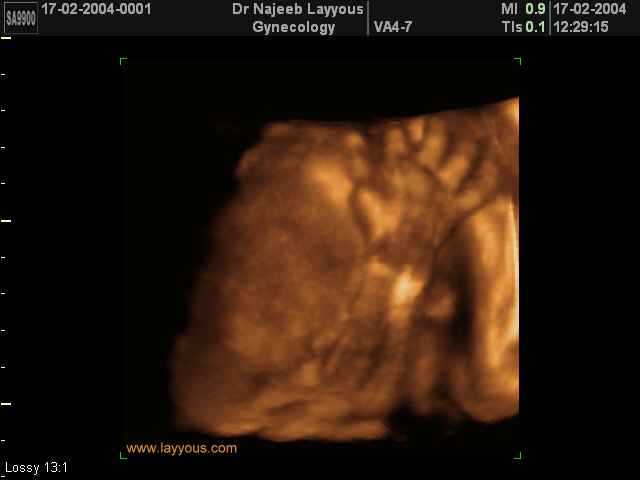

- تصرفات الجنين داخل الرحم

- صور لتصرفات الجنين داخل الرحم

- صور للجنين في المراحل المتوسطة من الحمل